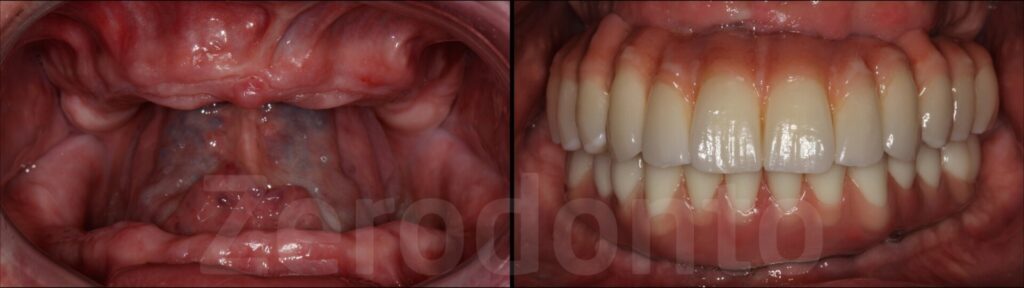

Elevate your dental care journey with our membership program, specifically designed for patients seeking teeth implants. As a member, you’ll benefit from reduced pricing on implant procedures, priority scheduling for consultations and treatments, and continuous follow-up care to ensure the best outcomes. Join today to access top-tier dental implant services and enhance your smile with confidence.